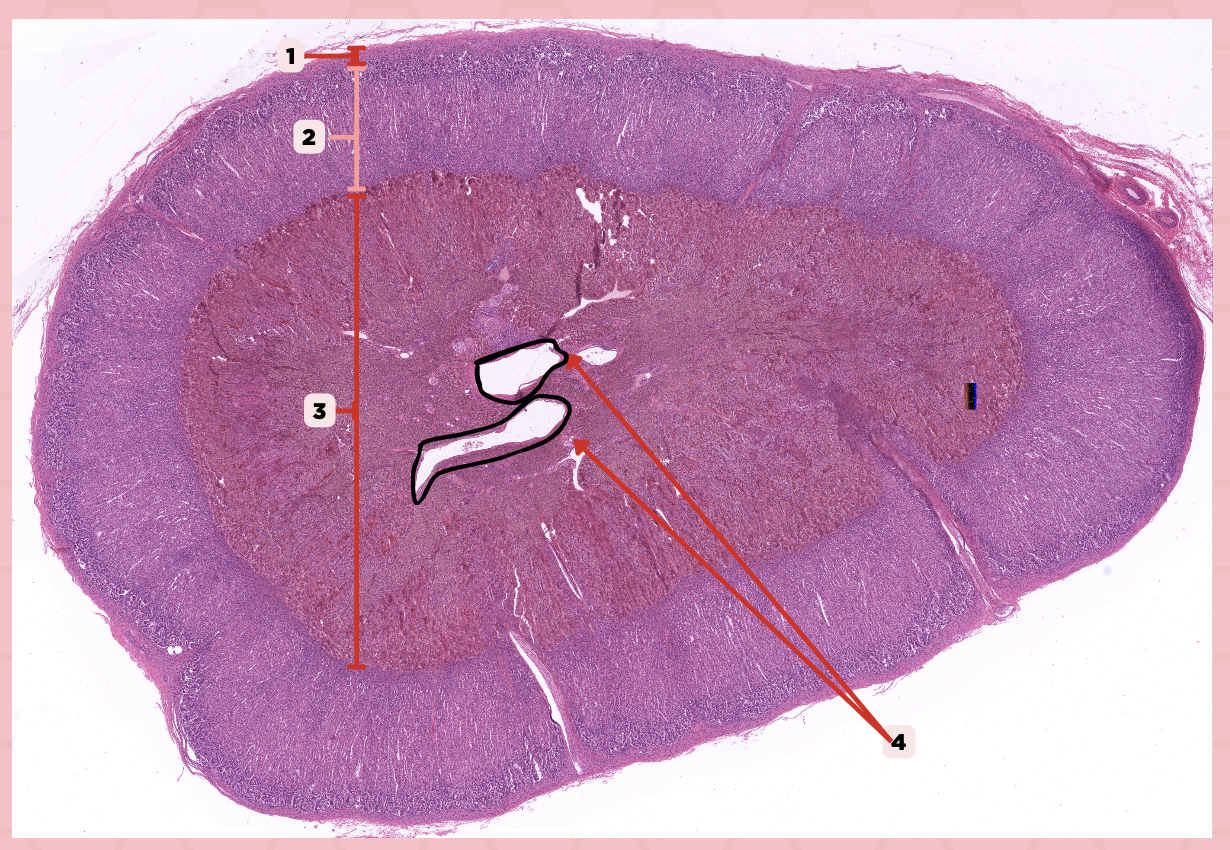

Adrenal

Identify the specimen.

Connective Tissue Capsule

Identify the structure labeled as 1.

Cortex

Identify the structure labeled as 2.

Medulla

Identify the structure labeled as 3.

Medullary Veins

Identify the structure labeled as 4.

Zone glomerulosa, Zone fasciculata, Zona reticularis

What are the zones present in pointer #2?

Catecholamines

What hormones are produced by pointer #3?